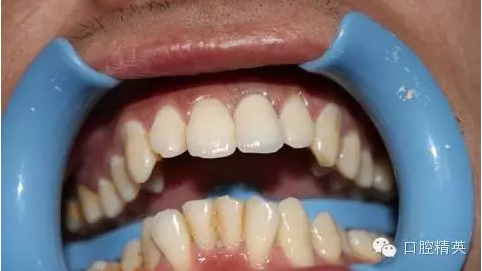

一年輕小伙,在打籃球中,被隊友打斷門牙,來本診所時已經(jīng)露髓,局麻拔髓后,行RCT。后因經(jīng)濟關(guān)系,擬鈷鉻樁加鈷鉻烤瓷冠修復(fù),備牙后才留照片:

7:試戴烤瓷牙,鈷鉻瓷牙,瓷肩臺處理

8:頸緣檢查

9:完全就位

10:黏結(jié)后,側(cè)面觀